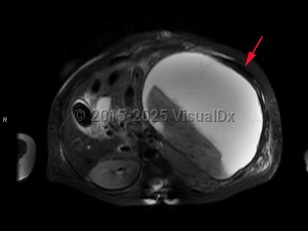

Splenic infarctionSplenic infarction